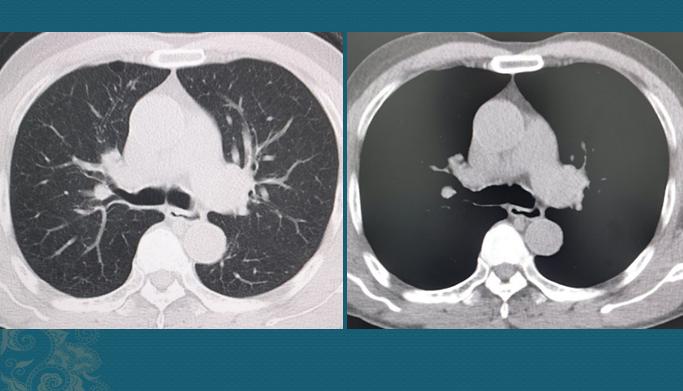

从生长速度上看,肺鳞癌通常比腺癌更快,破坏力更大(某些低分化腺癌也很快)。我们搜索这位病人既往的检查资料,发现他2年前因为感冒、咳嗽、发热做过一次胸部CT,当时的支气管和肺脏是完全正常的:

就是说,这个4.6cm的肿块是在不到两年的时间里长出来的,速度相当快!